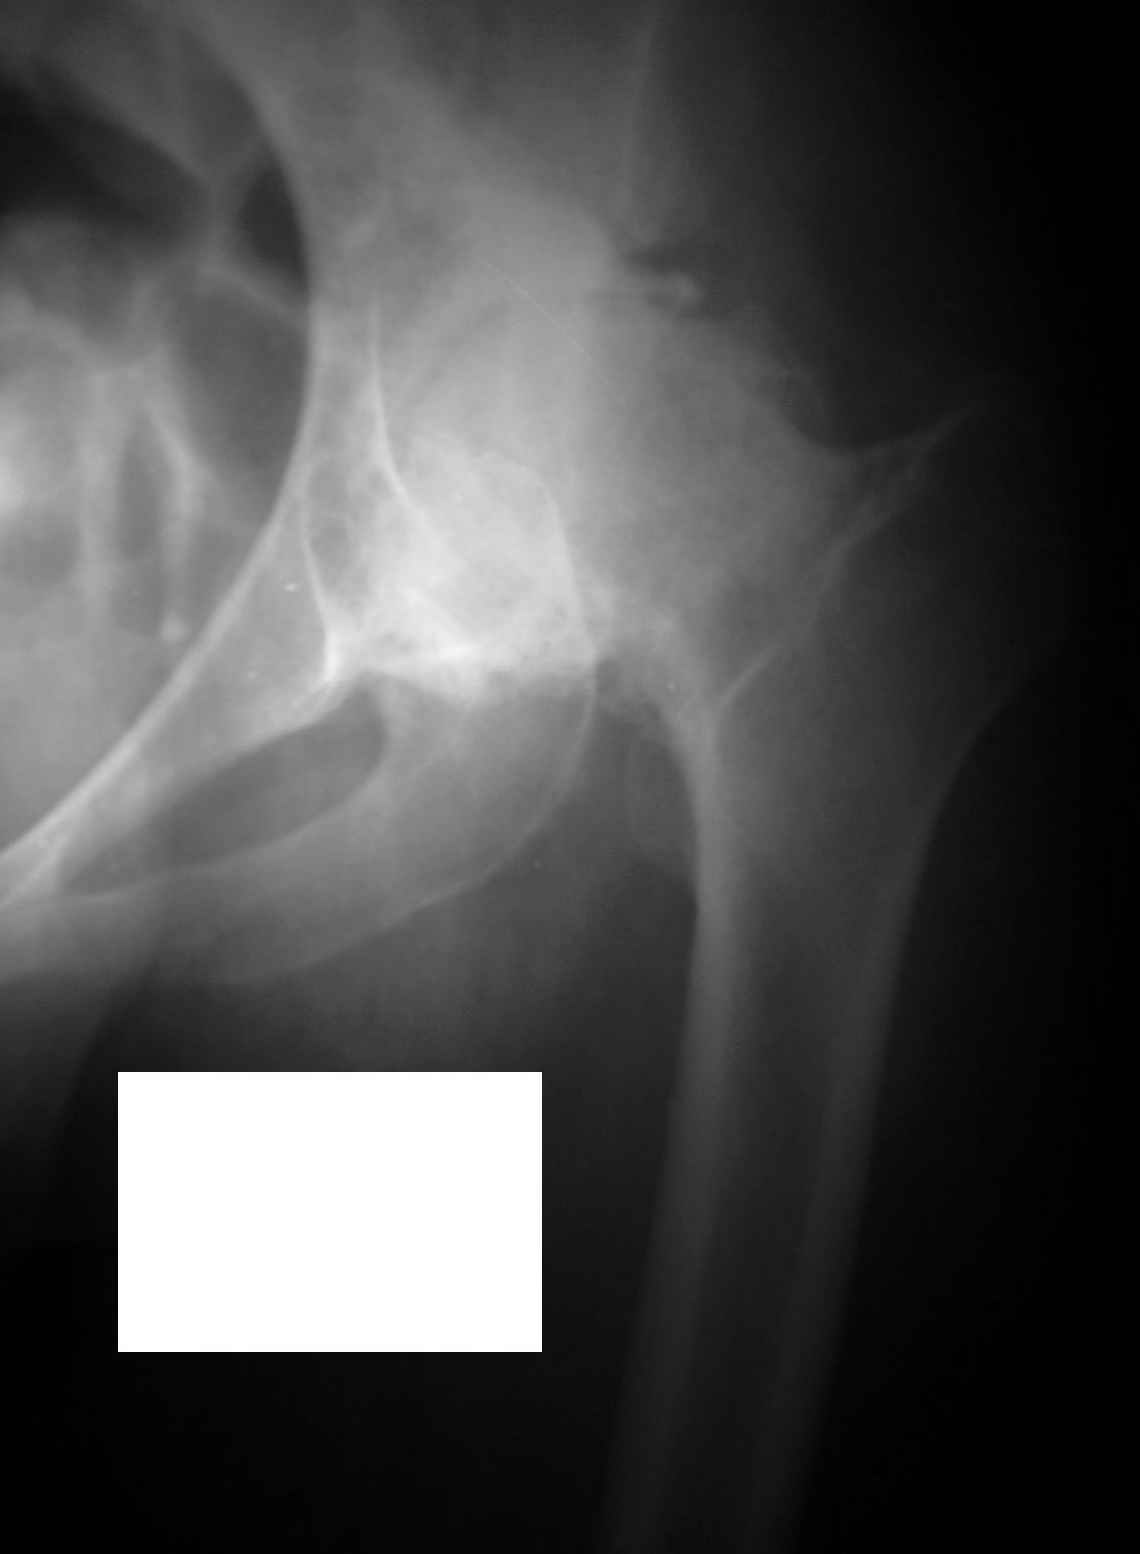

Извините, Анатолий, головка не выглядит потерянной, укорочение 5 см из-за порочного положения. Подход у молодой женщины я бы выбрал в зависимости от мобильности сустава.

На ригидном суставе межвертельная остеотомия для женщины мало привлекательна, но при гипомобильности, а тем более мобильности сустава вполне пригодна. И эффект от операции мы наблюдаем больше 10 лет и для последующего эндопротезирования трудности не велики, если остеотомию правильно спланировать и выполнить (проксимальный отдел бедра после остеотомии должен соответствовать нормальной анатомической геометрии). Привожу, что под рукой - Ртг 1997 ( даме 27 лет) и 2004 года. А моделей эндопротезов бесцементной фиксации для такой рентгеноантомической формы коксартроза действительно достаточно.

Учитывая молодой возраст женщины,аналогично менению глубокоуважемного В.П. Волошина, считаю оптимальным выполнить межвертельную корригирующую остеотомию бедра с небольшой медиализацией, тенотомией сгибателей и приводящих мышц бедра. Устранение порочного приведения, сгибания и ротации на остотомии позволит выровнять длину ног, так как здесь ортопедическое укорочение за счет фиксированного приведения и сгибания бедра. Фиксацию фрагментов можно выполнить аппаратом Илизарова, что позволит обойтись без иссечения костного клина и в полеоперационном периоде будет возморжна остаточная коррекция, если что-то не удалось на операционном столе. Эффект от корригирующих медиализирующих остеотомий (уменьшение и ликвидация болевого синдрома, увеличение движений в сустве)по нашему опыту составляет от 7 до 10 лет, что позволяет отсрочить выполнение эндопротезирования. Система для имплантации, действительно, может быть любая, выбор большой, но, на наш взгляд, предпочтительна бесцементная.